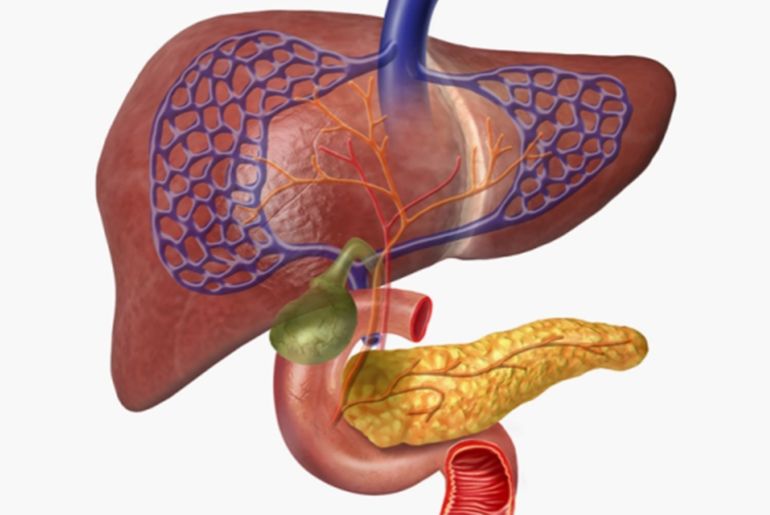

طوّر فريق دولي من الباحثين ولأول مرة نموذجا لخلايا جزر البنكرياس البشرية المشتقة من الخلايا الجذعية ذات الأوعية الدموية المتكاملة. والجزر هي مجموعات خلوية في البنكرياس تضم أنواعا مختلفة من الخلايا المفرزة للهرمونات، بما فيها خلايا بيتا المنتجة للإنسولين.

ووجد باحثون، أن عضيات خلايا جزر البنكرياس الجذعية المزودة بأوعية دموية تحتوي على أعداد أكبر من خلايا بيتا الناضجة، وتفرز إنسولينا أكثر من نظيراتها غير الوعائية. وقد حاكت العضيات الوعائية خلايا جزر البنكرياس الموجودة في الجسم بشكل أدق. والعضيات هي أعضاء صغيرة تحاكي مجموعات الخلايا المنتجة للإنسولين خارج الجسم.

تُستخدم عضيات خلايا جزر البنكرياس الجذعية على نطاق واسع لدراسة مرض السكري وأمراض الغدد الصماء البنكرياسية الأخرى. لكن خلايا بيتا في هذه العضيات عادة ما تكون غير ناضجة، مما يجعلها نماذج غير مثالية للبيئة داخل الجسم، كما تقول ساندر. وتضيف أنه على الرغم من تطوير العديد من الأساليب لتعزيز نضج خلايا بيتا، إلا أن آثارها كانت متواضعة.

لمحاكاة البيئة داخل الجسم الحي أفضل، أضاف الباحثون خلايا بطانية بشرية، تُبطّن الأوعية الدموية، وخلايا ليفية، وهي خلايا تُساعد في تكوين النسيج الضام، إلى عضيات الجزر التي تم تنميتها من الخلايا الجذعية.